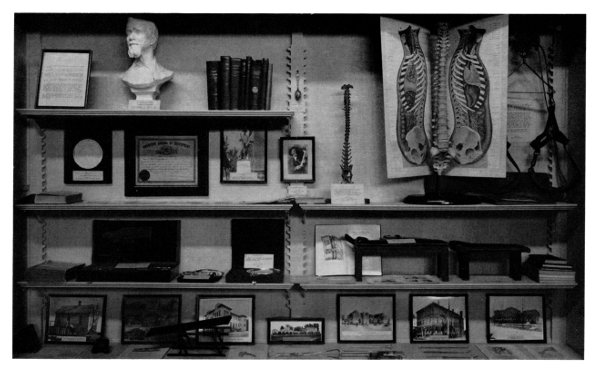

| 43. | History of the Division of Medical Sciences Sami Hamarneh |

269 |